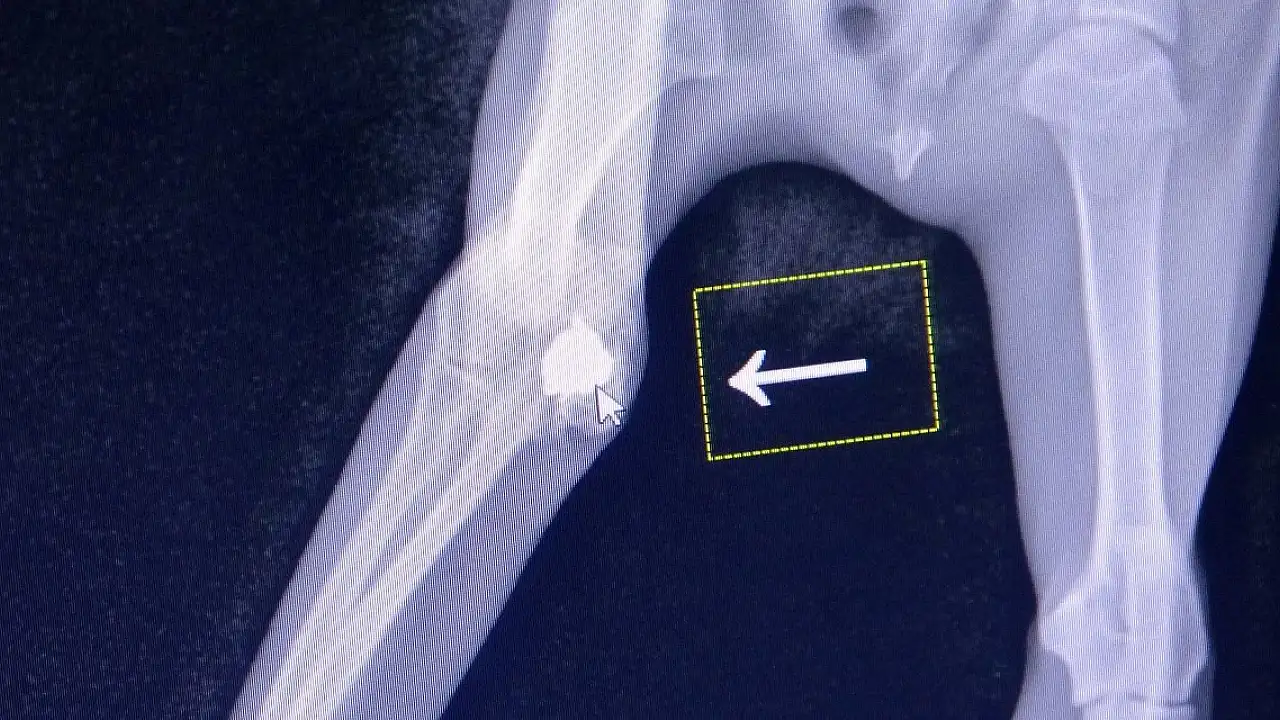

Keşan'a bağlı Erikli köyü sahilinde sağ ön bacağını kullanamayan ve topallayarak yürüyen yavru kediyi gören hayvanseverler, durumu Keşan Sokak Hayvanlarını Koruma Derneği (KE-HAYKO) yetkililerine bildirdi. Dernek yetkililerince Erikli köyü sahilinden alınan yavru kedi, Keşan'daki özel bir kliniğe getirildi. Burada yapılan muayene ve çekilen röntgen filminde yavru kedinin havalı tüfekle sağ ön bacağından vurulduğu ve saçmanın diz kapağına girmesi sonucu yaralandığı belirlendi. Saçma çıkarılamazken, yavru kedinin ömrü boyunca topallayarak yürümek zorunda kalacağı bildirildi.

Veteriner Hekim Berk Canbaz, yavru kedinin kendilerine trafik kazası geçirdiği gerekçesiyle getirildiğini ancak yapılan tetkiklerde sağ ön bacağından havalı tüfekle vurulduğunun belirlendiğini ifade ederek, "Ayağında topallama şikayetiyle geldi. Yapılan muayeneden sonra röntgen çektik. Röntgen sonucunda da sağ ön bacağı diz kapağı bölümünde saçma olduğunu gördük. Ekleme saplanmış bir şekildeydi. Müdahale edilebilecek veya operasyonla çıkarılabilecek bir durumda değildi. Topallama şikayeti devam edecektir ama o bölgeye müdahale etmemiz mümkün değil. Yaptığımız incelemede gördük ki havalı tüfekle vurulmuş. Ömür boyu bu saçmayla yaşamak zorunda kalacak. Çünkü saçmayı o bölgeden aldığımızda eklemin dağılması söz konusu. Bu da bacağını kaybetmesine kadar gidebilir. Maalesef ömür boyu topallayarak yaşayacak" dedi.